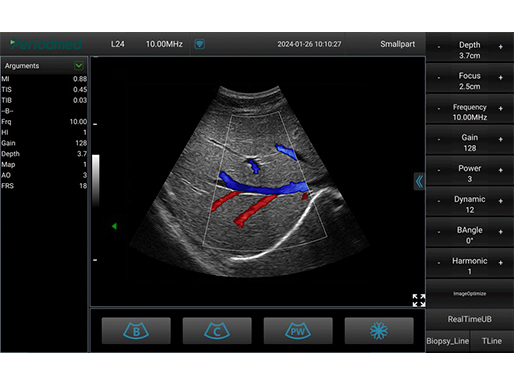

彩色模式 甲状腺

彩色模式 甲状腺

彩色模式 甲状腺